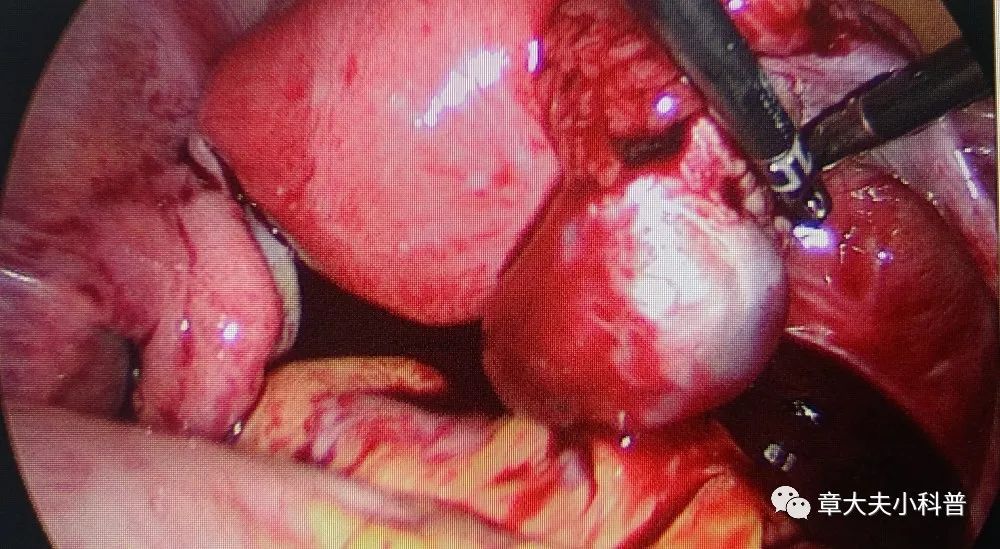

腹腔镜探查

见右侧卵巢

黄体破裂,

腹腔内出血,

1300ml